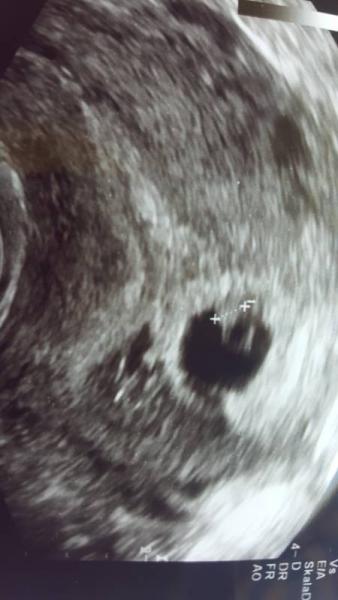

So sie meinte ich hätte einen riss von 1cm ist ein bluterguss ist auch nur 1 baby anstatt 2 bild füge ich bei

Bild zu